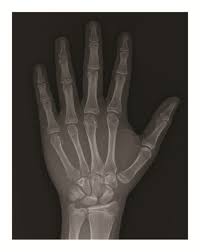

Think of the epiphyseal line as a permanent mark that tells us the bone has finished growing. You can see this line on an X-ray, and it’s helpful for doctors to determine bone age, which is particularly important for evaluating growth and development in children and adolescents.

For example, if a doctor sees that a child’s epiphyseal lines are still open, it means that the child is still growing. Conversely, if the epiphyseal lines are closed, it means that the child has reached their full height. This is also useful for understanding the healing process after a bone fracture. The presence of an epiphyseal line can help determine the location of the fracture and the extent of bone growth that has occurred since the injury.

The presence of an epiphyseal line on an x-ray indicates that the bone has finished growing in length.

When epiphyseal closure is complete, a line appears on the x-ray where the epiphyseal plate used to be. This line is called the epiphyseal line.

Epiphyseal lines are a good indicator that a person has reached their full height. They can also be useful for determining a person’s age, especially in children.

* When the epiphyseal plates are closed, the epiphyseal line appears on an x-ray.

The epiphyseal line is a good indication that bone growth in length has stopped. Epiphyseal closure happens at different times for different bones and people. It’s usually complete by the end of puberty, around age 18 for females and 20 for males.

Here’s the thing: we can’t actually see the growth plates directly. They’re inside the bone. But, we can use X-rays to see the epiphyseal line, which is like a ghost of the growth plate once it’s closed.

The epiphyseal line will show up as a thin, dense line on the X-ray. It’s not super obvious, but an experienced doctor or radiologist can spot it.